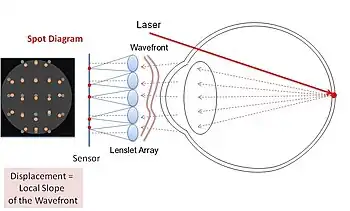

A Shack–Hartmann (or Hartmann–Shack) wavefront sensor (SHWFS) is an optical instrument used for characterizing an imaging system.[1][2] It is a wavefront sensor commonly used in adaptive optics systems. It consists of an array of lenses (called lenslets) of the same focal length. Each is focused onto a photon sensor (typically a CCD array or CMOS array[3] or quad-cell[4]). If the sensor is placed at the geometric focal plane of the lenslet,[5] and is uniformly illuminated,[6] then, the integrated gradient of the wavefront across the lenslet is proportional to the displacement of the centroid. Consequently, any phase aberration can be approximated by a set of discrete tilts. By sampling the wavefront with an array of lenslets, all of these local tilts can be measured and the whole wavefront reconstructed. Since only tilts are measured the Shack–Hartmann cannot detect discontinuous steps in the wavefront.

Shack–Hartmann sensors are used in astronomy to measure telescopes and in medicine to characterize eyes for corneal treatment of complex refractive errors.[9][10] Recently, Pamplona et al.[11] developed and patented[12] an inverse of the Shack–Hartmann system to measure one's eye lens aberrations. While Shack–Hartmann sensors measure the localized slope of the wavefront error using spot displacement in the sensor plane, Pamplona et al. replace the sensor plane with a high resolution visual display (e.g. a mobile phone screen) that displays spots that the user views through a lenslet array. The user then manually shifts the displayed spots (i.e. the generated wavefront) until the spots align. The magnitude of this shift provides data to estimate the first-order parameters such as radius of curvature and hence error due to defocus and spherical aberration.